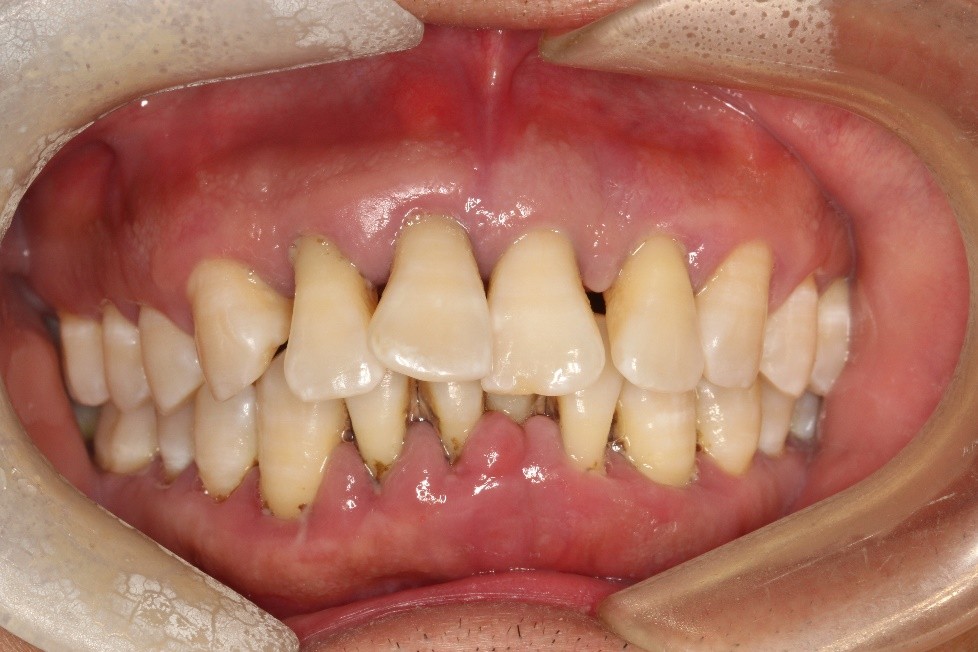

先给大家看一张牙周情况糟糕的图片。

从图片就能看出,这位34岁的男子牙周情况很差—— 牙结石积多,牙龈红肿发炎,牙齿松动,牙根暴露。

经过牙周治疗,牙周恢复到稳定状态后,我院正畸一科狄耀云医生才对其进行矫正。

最终他 牙列恢复整齐,整个人年轻了好几岁。